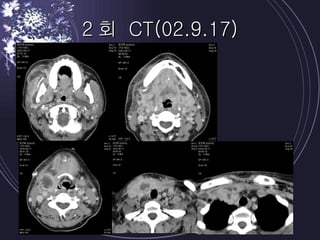

2회 CT(02.9.17)

Case report 1Pt ; 38/F CC ; 내원 5 일 전 개인치과 발치 후 우측 swelling 으로 내원 PI ; mouth opening limitation, dysphagia, Rt buccal & sub mn swelling / Td/ redness Dx ; masticatory spce, lat. Pharyngeal space abscess Tx ; I & D X 2 (submn & submental, deep neck carotid sheath area) anti theraphy ( aug + micronomycin + flagyl) fluid etc supplementary tx (O2 etc) 초진 lab ; WBC 30260, segmental neutrophil 85.9%, CRP 36.5